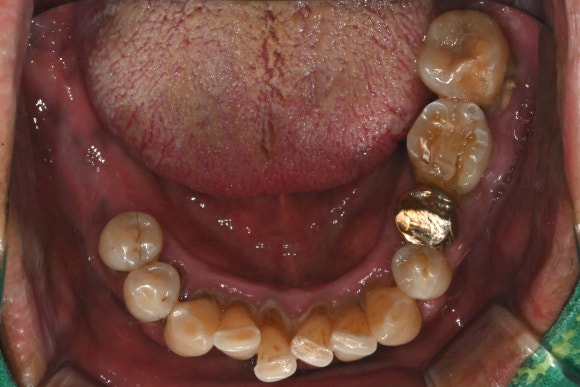

엑스레이를 찍어보니,

아래 앞니는 풍치로 인해

잇몸뼈가 많이 녹아 있었고

아래 어금니 쪽도

이미 뼈 흡수가 진행된 상태였습니다.

전체적으로 치아가 이제는

버티기 어려운 단계라고 할 수 있죠..

수술 전 후 사진을 비교해보면

더욱 명확히 들어납니다.